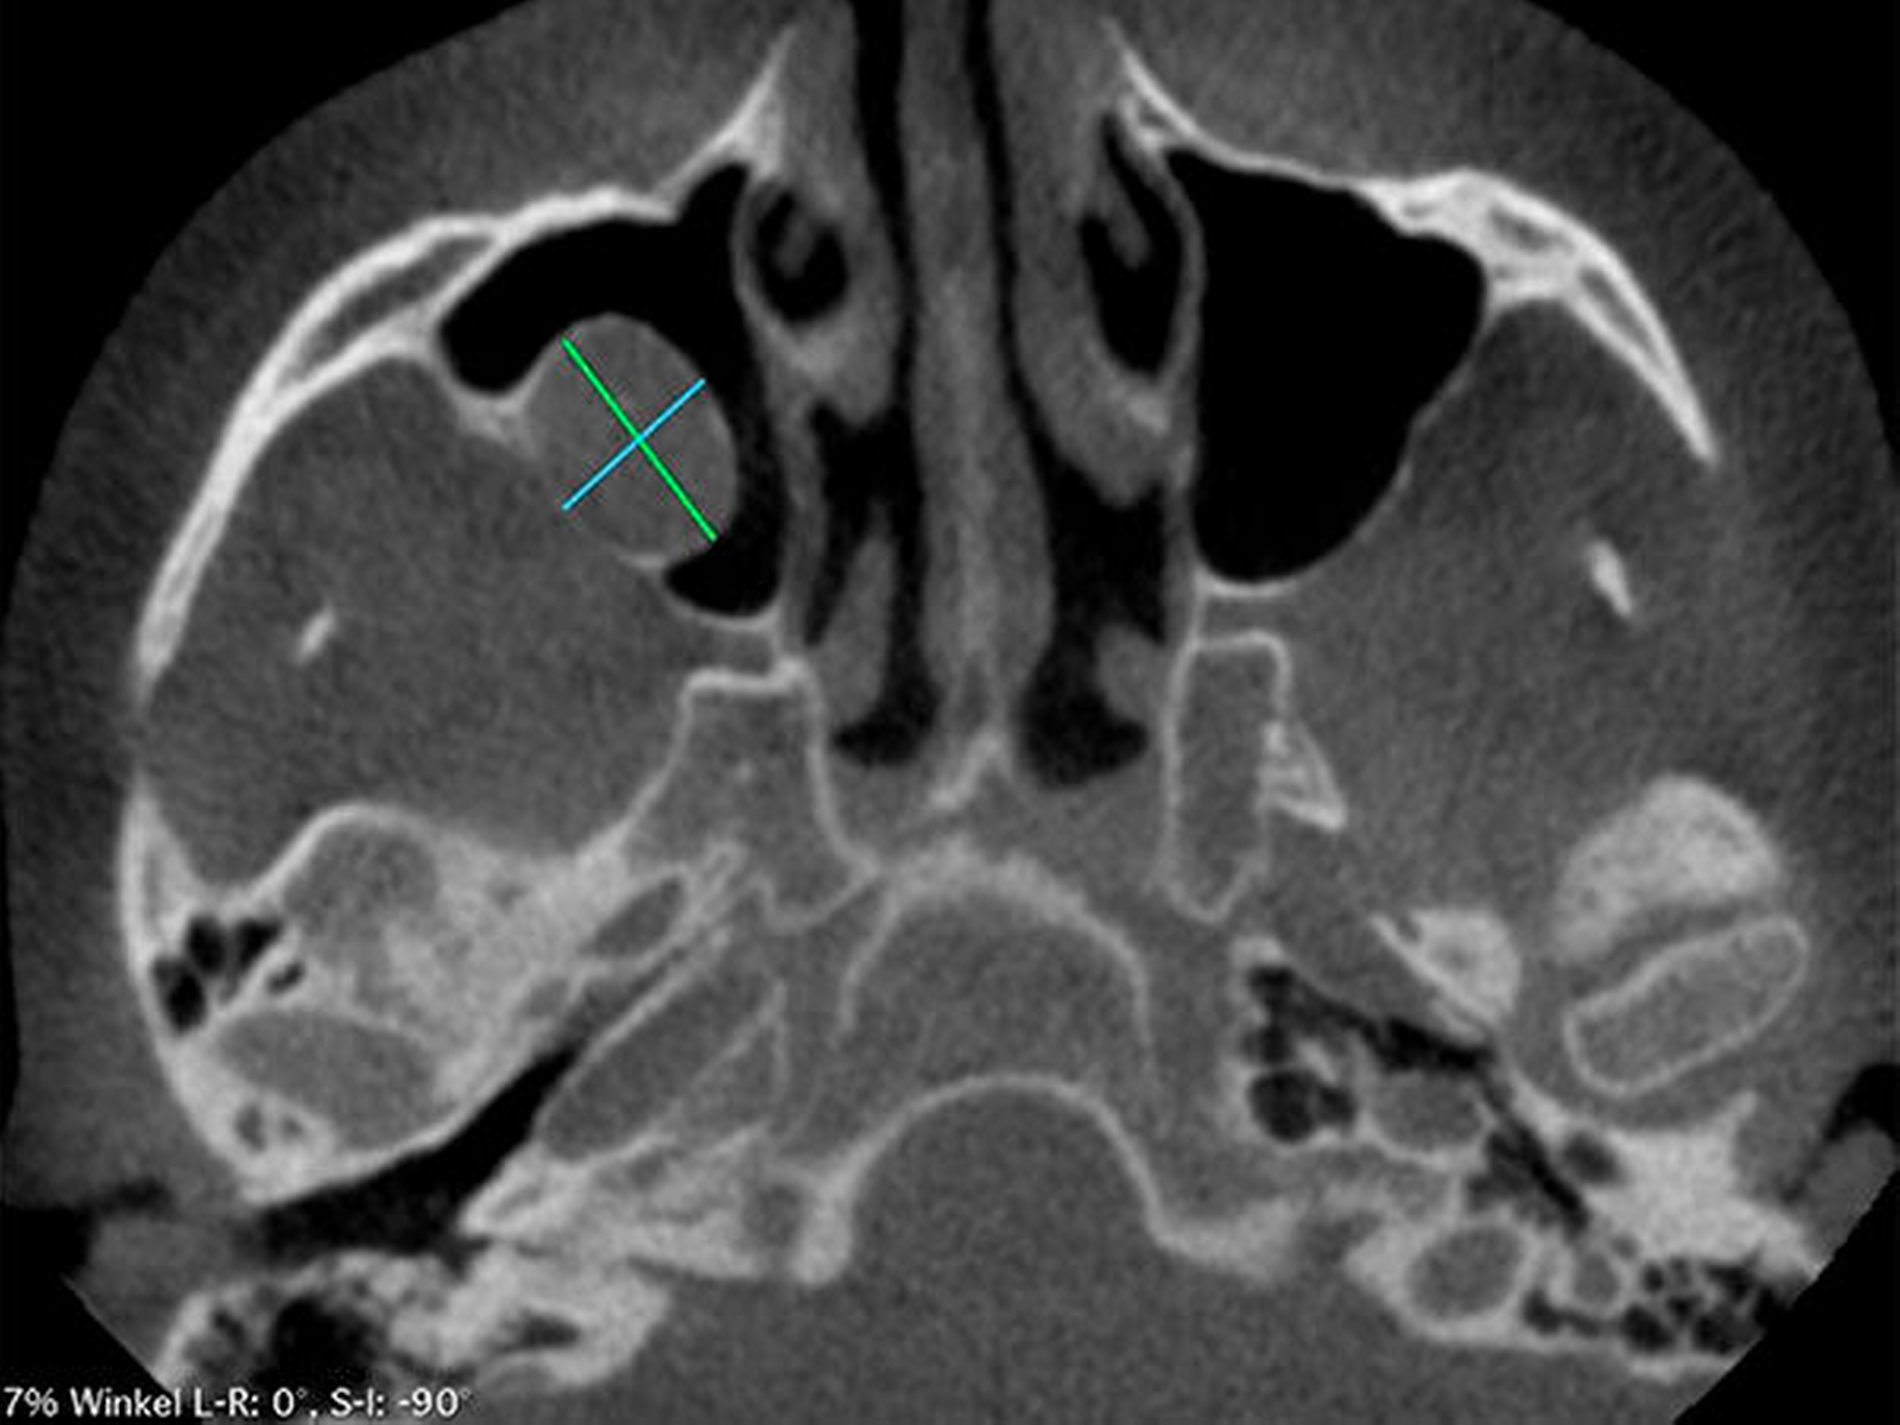

Die Durchführung einer digitalen Volumentomografie (DVT) zeigte die dreidimensionale Ausdehnung der eiförmigen Raumforderung mit einem Volumen von 2,34 cm3 (Abbildung 2).